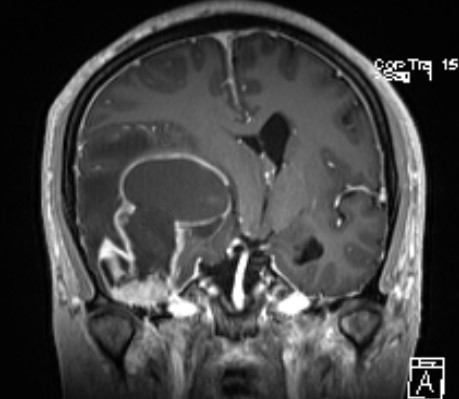

术后复查肿瘤近全切除

术后病理:弥漫性胶质瘤高级别

患者术后恢复良好,肢体活动可,能自主下床活动